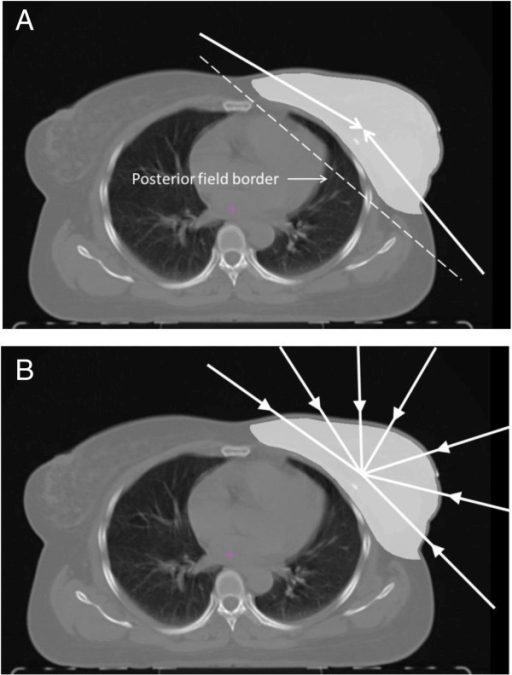

또한 폐암 치료에서도 주변 정상 폐 조직의 손상을 최소화하면서 종양에 방사선을 정밀하게 조사하는 것이 필수적입니다. 이를 위해 입체적 방사선 치료(3D CRT)와 같은 고급 방사선 치료 기법이 사용됩니다. 해당 방법은 정밀한 이미지 처리 기술을 활용하여 종양의 형태와 위치를 정확히 판단하고, 이를 기반으로 방사선 치료 계획을 세웁니다. 이를 통해 필요한 부위에만 집중적으로 방사선을 전달함으로써 주변 정상 조직의 방사선 노출을 획기적으로 줄일 수 있습니다.